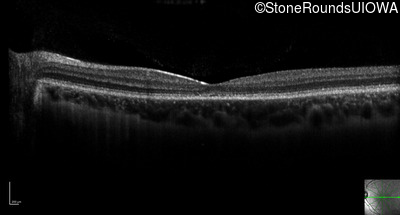

Optical Coherence Tomography - Left - 20/25 -2 sc

Exemplar / OCT Stack